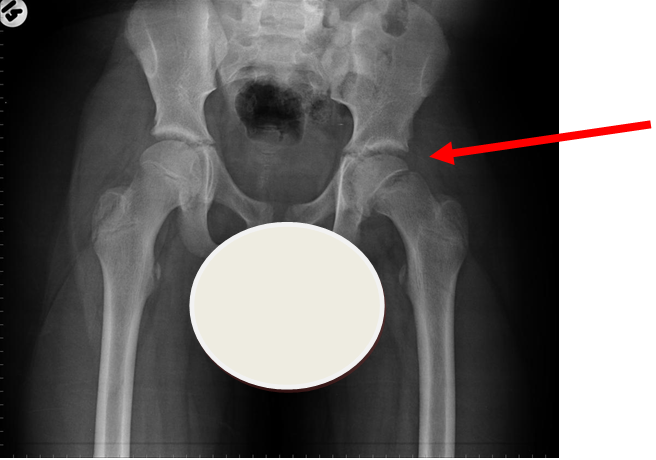

More obvious left sided SUFE (AP)

Case courtesy of Dr Gagandeep Singh, Radiopaedia.org. From the case rID: 7228

Usually occurs in late childhood / adolescence and is more common in boys than girls (2:1). It also presents more commonly in children whose weight is above the 90th centile. Bilateral in 25% of cases. Onset can be acute or subacute (ie children may present with >1day h/o pain or limp). Children may walk with an antalgic gait out-toeing, with shortening of the affected limb. If the slip is acute, the child may be unable to walk. Diagnosis is made radiologically and frog-lateral views are required as it may be missed on AP views. Urgent orthopaedic opinion is required. Unstable slips can lead to avascular necrosis of the femoral head.

Investigation

- X-ray - AP pelvis with frog lateral view (must be discussed with ortho 1st on call / ED consultant if child <8 years old)